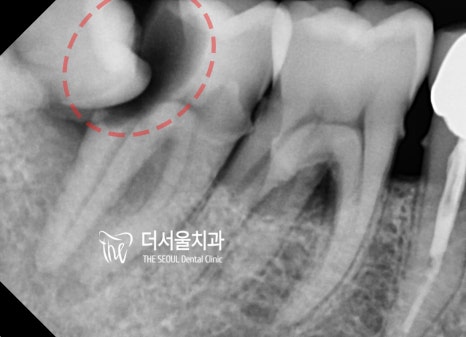

조금 더 확대해서, 해상도 높은 엑스레이로 보면

좌측사진에서는 치관의 1/2 가량이 썩어있는 것과